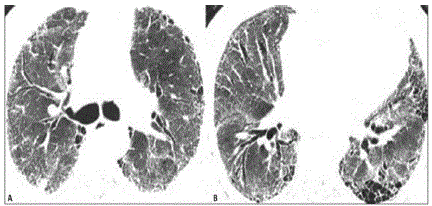

Você está diante de um paciente portador de fibrose pulmonar idiopática, última tomografia mostrada abaixo, com prognóstico reservado em relação à doença de base, familiares conscientes da situação. Diante do quadro de exacerbação aguda da doença, o que é melhor indicado?